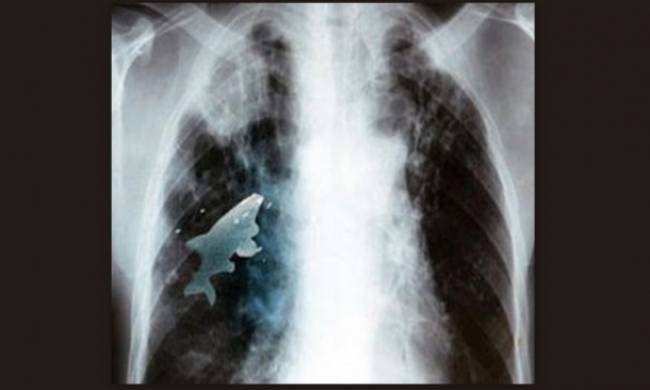

Ψάρι κολυμπούσε μέσα στον πνεύμονα 12χρόνου!

Μπορεί να σας ακούγεται απίστευτο είναι όμως πέρα για πέρα αληθινό! Η ιστορία αυτή σίγουρα θα περάσει στην ιστορία καθώς είναι από τις ελάχιστες φορές που έφηβος χειρουργείται για να του αφαιρέσουν από τον πνεύμονα του ένα ζωντανό ψάρι! Καλά ακούσατε! Ο έφηβος Ινδός, όπως αναφέρει το mothersblog, καθώς έπαιζε δίπλα σε έναν ποταμό, έκανε κάτι που συνηθίζουν στην Ινδία, κατάπιες ένα ζωντανό ψάρι αλλά αντί να καταλήξει στο στομάχι του νεαρού, πήγε στον πνεύμονα. Ευτυχώς ο πιτσιρικάς αντιλήφθηκε αμέσως ότι κάτι δεν πάει καλά καθώς δεν μπορούσε να αναπνεύσει κι έτσι οι γιατροί προχώρησαν σε χειρουργείο απ' όπου και αφαίρεσαν το εννέα εκατοστών ψάρι. «Το ψάρι ήταν ζωντανό μέχρι που το αφαιρέσαμε, γεγονός που περιόριζε τη λειτουργία των πνευμόνων του αγοριού και του στερούσε οξυγόνο», δήλωσε ένας από τους γιατρούς!